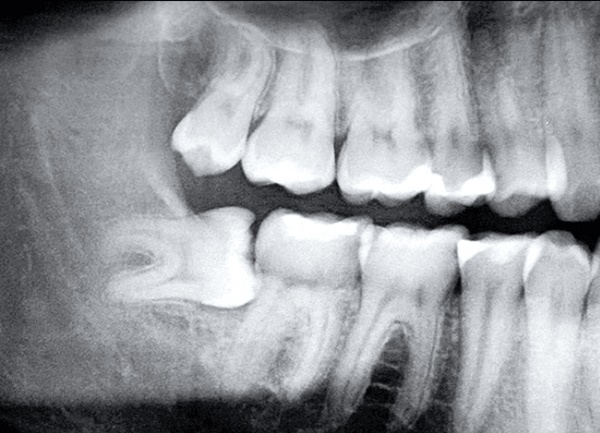

(Ảnh minh họa)